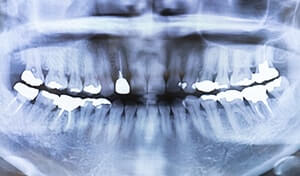

お口の中は一見きれいに見えても、歯の内部や骨の状態までは肉眼では確認できません。

レントゲンを撮ることで、虫歯の進行具合、歯の根の形や位置、顎の骨の状態、歯周病の進行度、さらにはお子さまの歯の生え変わりの様子まで、見えない部分の情報を正確に把握できます。

これらの情報をもとに、より適切な治療計画を立てることができるのです。